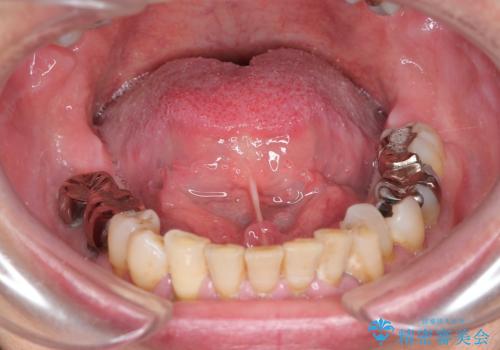

最新の症例

Latest cases